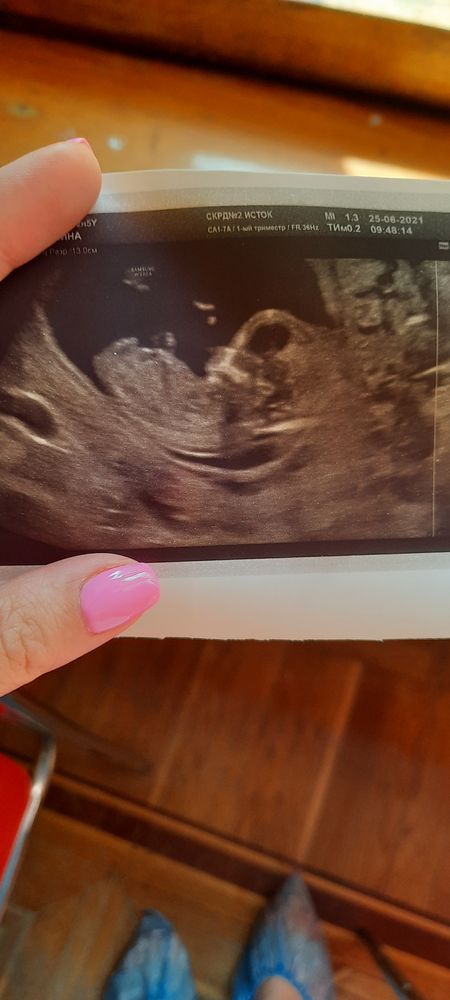

Итак, сегодня 12+5, первый триместр позади, сегодня был первый скрининг и сдача анализов на генетические отклонения.

По узи у нас все хорошо, малютка шевелится, ручками личико трогает, все органы в норме. Опережаем на неделю (13+4). Так приятно было смотреть на экран монитора !!! Мы очень хотим девочку, но предположили, что мальчик, (в конце прям поймала ключевой орган), но сказали не терять надежду, вдруг на следующем узи все таки девчонка окажется,🙏. Но если пацан, то можно открывать футбольную школу🤣🤣, у нас у всех в семье по 2 пацана, только у брата одна девчонка выстрелила

А так, предподожу на 90 % что мальчик. Как обьснила моя узистаа, что пальчики в такой период более лобастве. Как у вас на фото))